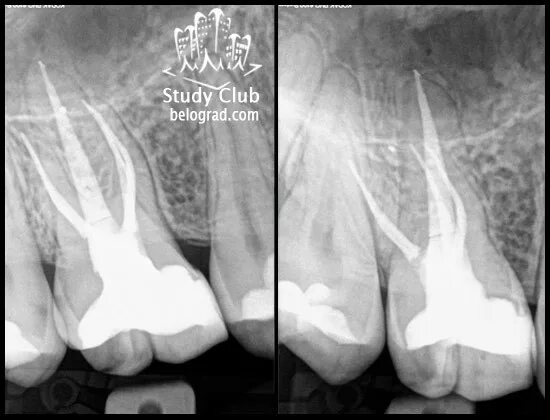

Перелечивание каналов зуба. пломбировочный материал вышел за пределы канала зуба. если перелечить каналы зуба.

Обтурация корневого канала рентген. пульпит 17 зуба рентген с запломбированными каналами. пломбировка каналов зуба рентген.